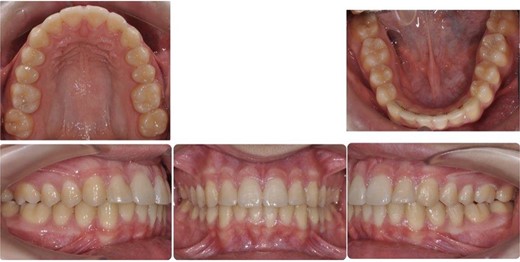

Post-treatment clinical examination showed that crowding was relieved by a 4-mm increase in the intermolar width of the maxillary and mandibular arches. In addition, a class I molar and canine relationship was achieved with good occlusion (Fig. 5) and a pleasing smile (Fig. 6). Post-treatment lateral cephalometric radiographs showed that the mandible had grown forward in the sagittal dimension, improving the skeletal profile (Fig. 7b). The upper incisors were proclined by 15° to achieve ideal labio-lingual inclination for optimum aesthetics; the lower incisor was optimally positioned to achieve ideal overjet and overbite (Fig. 7b). Mandibular anterior teeth were intruded to correct the impinging overbite and level the Curve of Spee. Finally, the patient was referred to an oral surgeon for extraction of the third molars.

Post-treatment intra-oral photos showing severe mandibular crowding